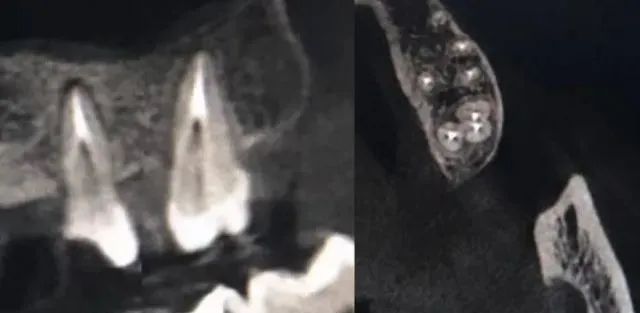

以上是兩種治療切片,是我去年最滿意的治療方法。在CBCT的指導下,根管治療從2D上升到3D的高度,更加嚴格和困難。它也給我們以後的效果帶來了更大的信心。如果有CBCT,可以好好研究一下系統的功能,功能很強大,一定有你沒發現的東西。

以上治療在根尖片和曲斷方面效果良好,但在ct下可以發現很多問題。這是cbct提出的更高標准。這篇文章是關于根管准備的。爲什麽要把測長放在第一位?這就是我們今天要了解的一個治療原則——保護根尖結構的根管准備方法。